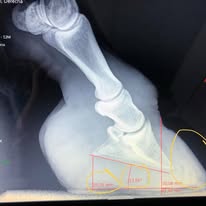

Formando Herradores y Podólogos Equinos desde 1996